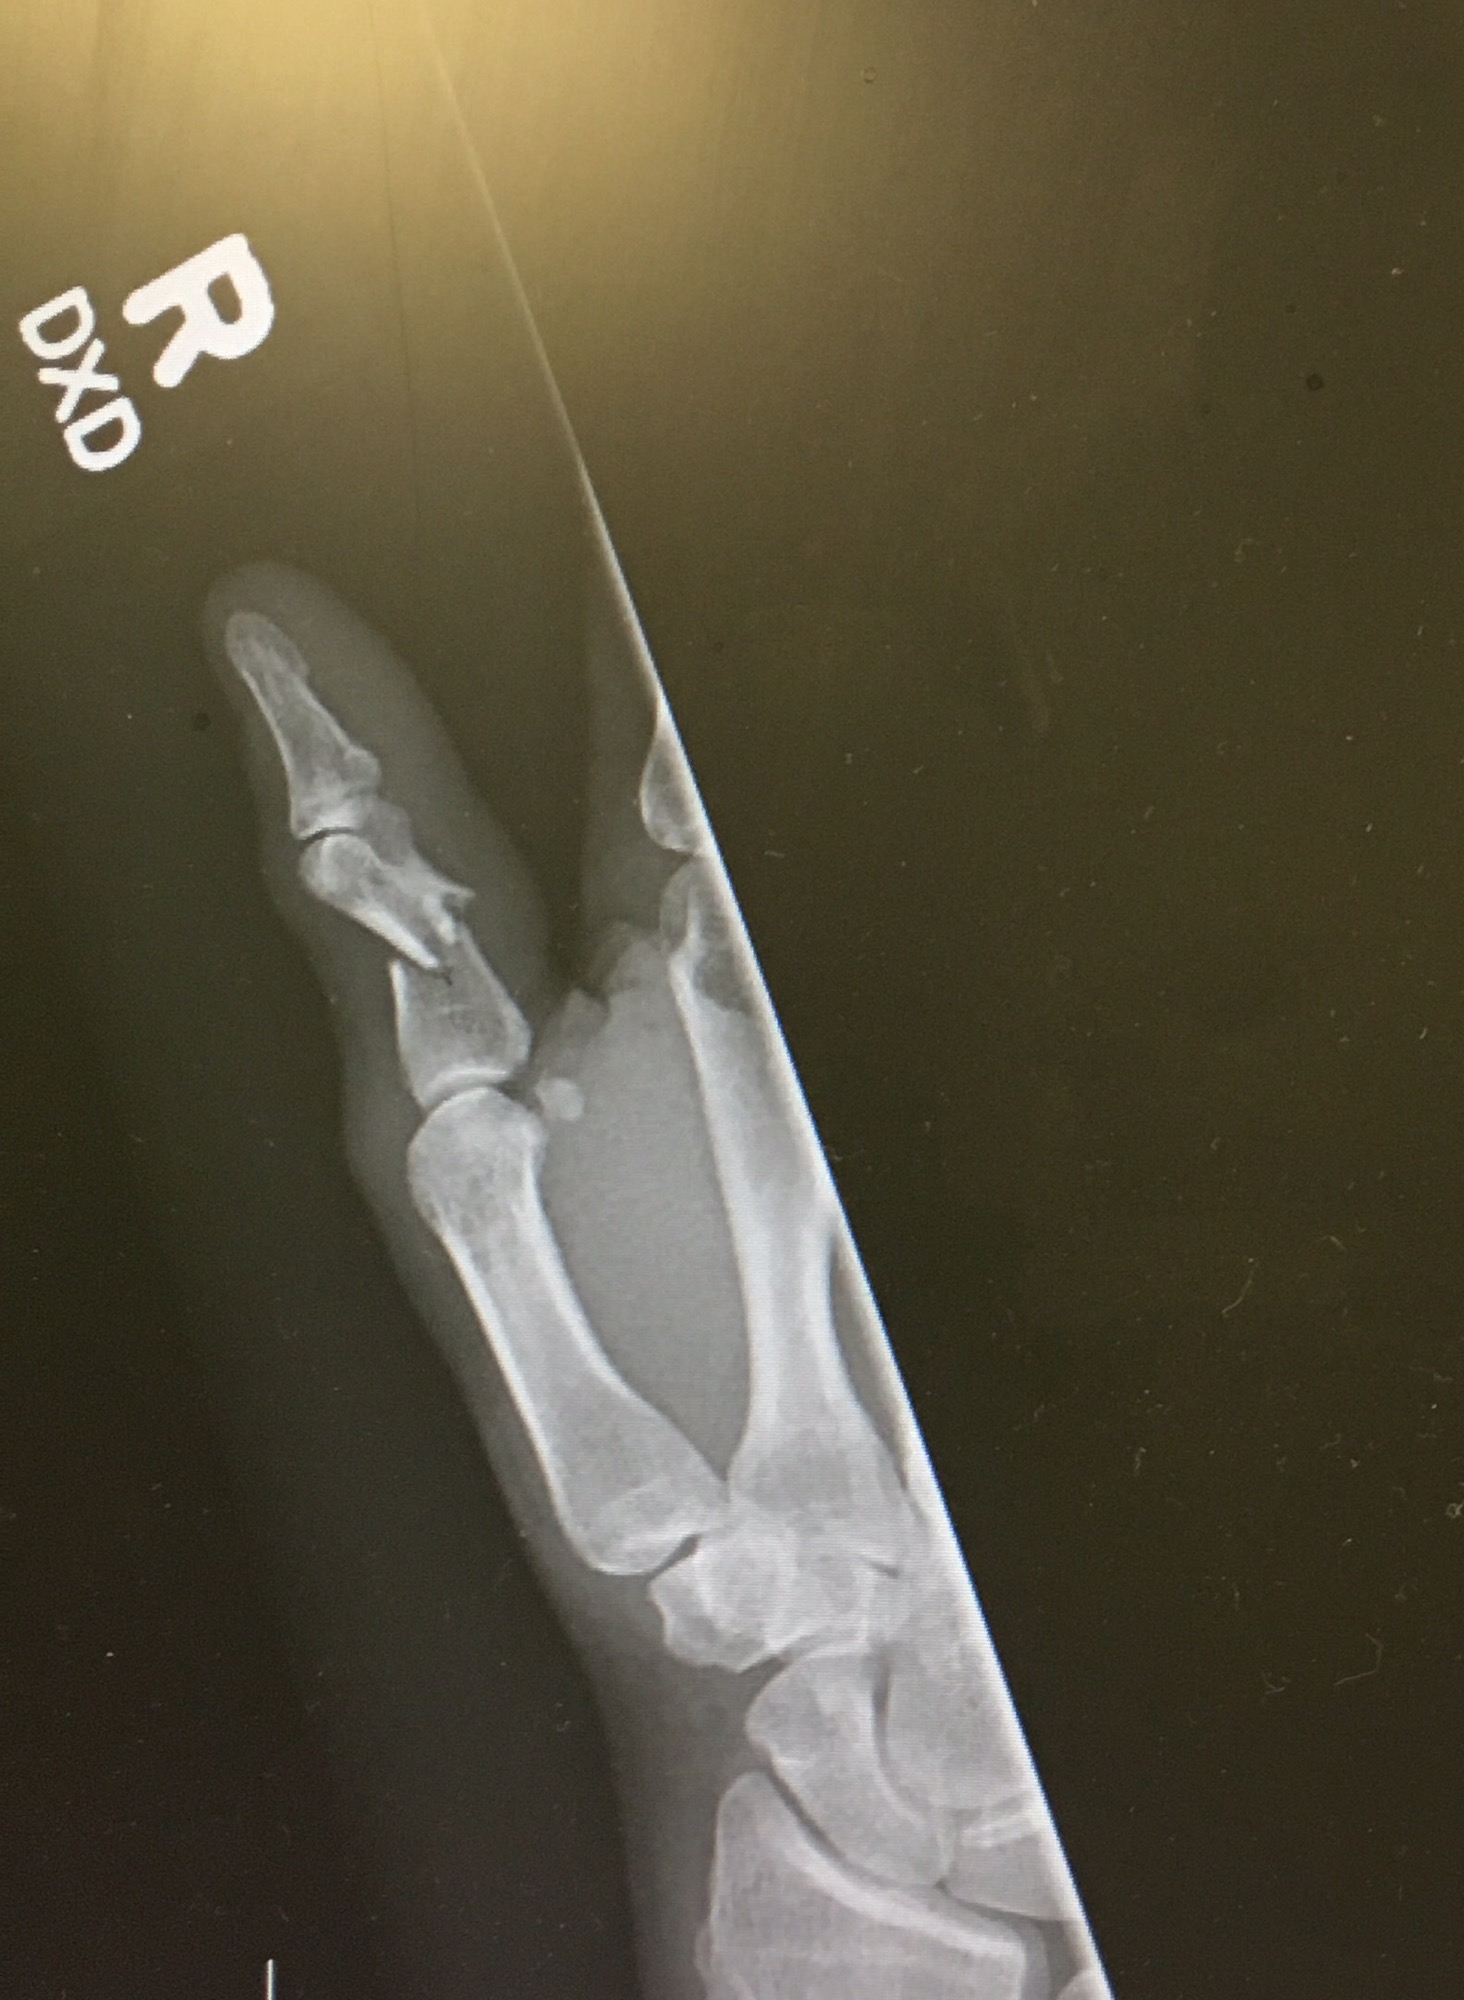

Fairly certain the middle of my thumb should not be pointing in two directions!

End result of a rather painful afternoon. Note to self, springs on clay throwers are really really strong. Long story short, while trying out my clay target thrower in the back yard….it threw me a broken thumb. More later after the meds wear off.